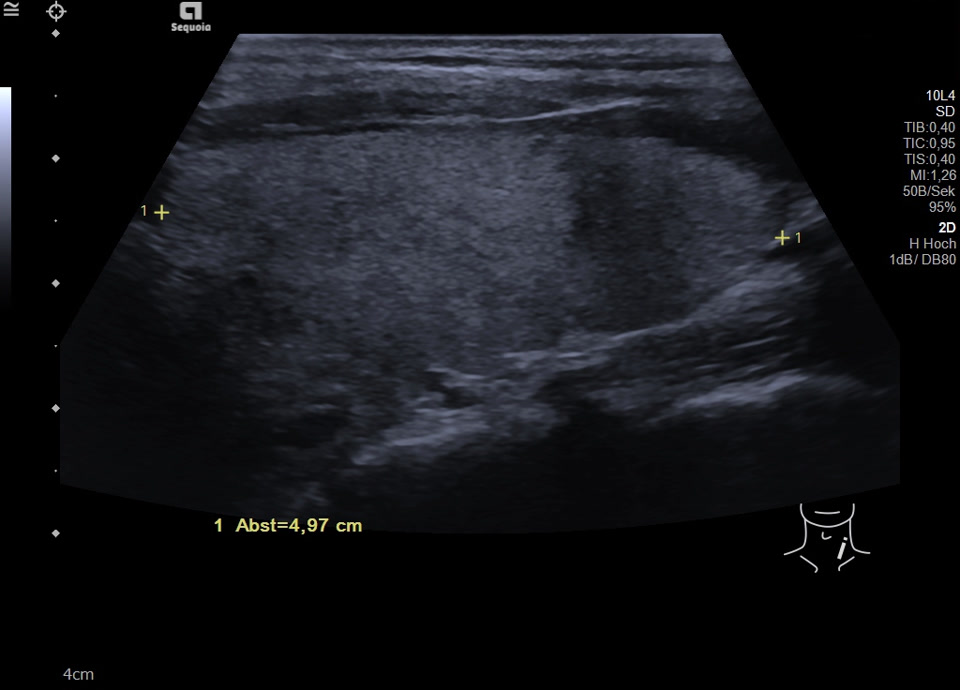

45-year-old male presented patient with persistent sore throat and general symptoms following an EBV-infection. An external diagnosis of post-infectious de Quervain’s thyroiditis had already been made, and a two-week course of corticosteroid therapy was administered. Initial clinical improvement with reduced throat pain was noted under treatment, but symptoms reoccurred after discontinuation of corticosteroids. Laboratory findings revealed leukocytosis of 12,000/µl and CRP of 113 mg/l. Sonographically, a bilaterally enlarged thyroid gland with diffusely hypoechoic areas and inhomogeneous parenchyma was observed. Combined with the patient history, this was characteristic of a subacute thyroiditis with relapse after short-term corticosteroid therapy. Prolonged corticosteroid therapy with slow tapering was performed. Under this regimen, marked clinical improvement occurred within weeks; follow-up ultrasound four months later showed a normal-sized thyroid with only mildly inhomogeneous parenchyma, consistent with resolving thyroiditis.